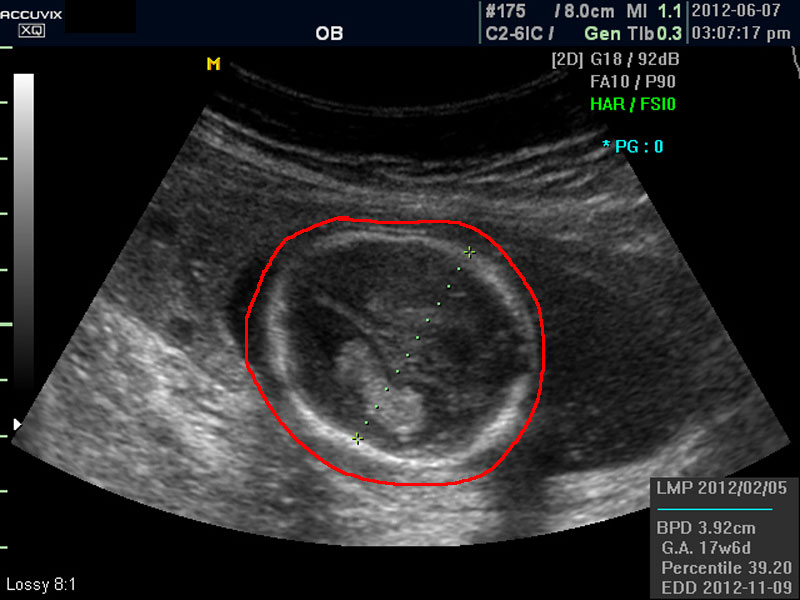

화면에서 좌측이 태아 머리 부분으로 빨간 펜으로 표시되어 있습니다.

초음파 상 태아의 머리가 좌측인가 우측인가 하는 것은 초음파 탐촉자의 위치를 어디에 두었느냐에 따라 다른 것 뿐으로 화면상 어디 위치하는 지는 중요하지 않습니다.

태아의 머리가 정상 모양인가 크기는 정상인가 하는 것을 살펴 본 후에는 태아의 크기를 측정하고 가슴, 복부, 엉덩이 부분, 상하지 부분이 정상인가 하는 것을 살펴 봅니다.

위 사진에서 빨간 동그라미로 표시한 부분이 태아의 머리를 위에서 내려다 본 수평 단면입니다.

하얗게 보이는 것은 뼈이고 내부에 검게 보이는 것은 뇌실에 고인 척수액 부분이며 내부의 하얀 부분은 뇌조직과 뇌실 내 맥락막이라고 하는 것입니다.

모든 사진에서 우측 하단에는 기본적인 발육 정보가 기록되는데 세번째 사진에서 빨간 펜으로 표시한 부분이며 그 내용의 의미는 아래와 같습니다.

참고로 이런 측정 수치가 나타나는 양식이나 위치는 초음파 장비마다 다르지만 용어는 대체로 공통된 의학 용어를 사용하기 때문에 대동소이합니다.

1. LMP

Last Menstrual Period의 약자로 최종 월경일입니다. 이런 최종 월경일을 바탕으로 현재의 임신 주수와 초음파상 측정 지표들간에 얼마나 괴리 되어 있나 하는 것을 판단하는 것입니다.

3. GA

Gestational Age의 약자로 우리말로는 임신 주기라고 하며 CRL이나 BPD등을 기준으로 했을때 임신 몇주 며칠에 해당하는 지 나타낸 것입니다.

4. BPD

Biparietal Diameter의 약자로 머리를 위에서 보아서 양쪽 옆통수에서 반대쪽 옆통수까지의 길이입니다.

이는 임신 중기부터 후기까지 태아의 발육을 판단하는 중요한 지표이며 태아의 체중을 예측하는 데 쓰이는 지표 중 하나입니다.

5.EDD

Estimated Due Date의 약자로 초음파 측정치를 바탕으로 산출한 출산 예정일입니다.